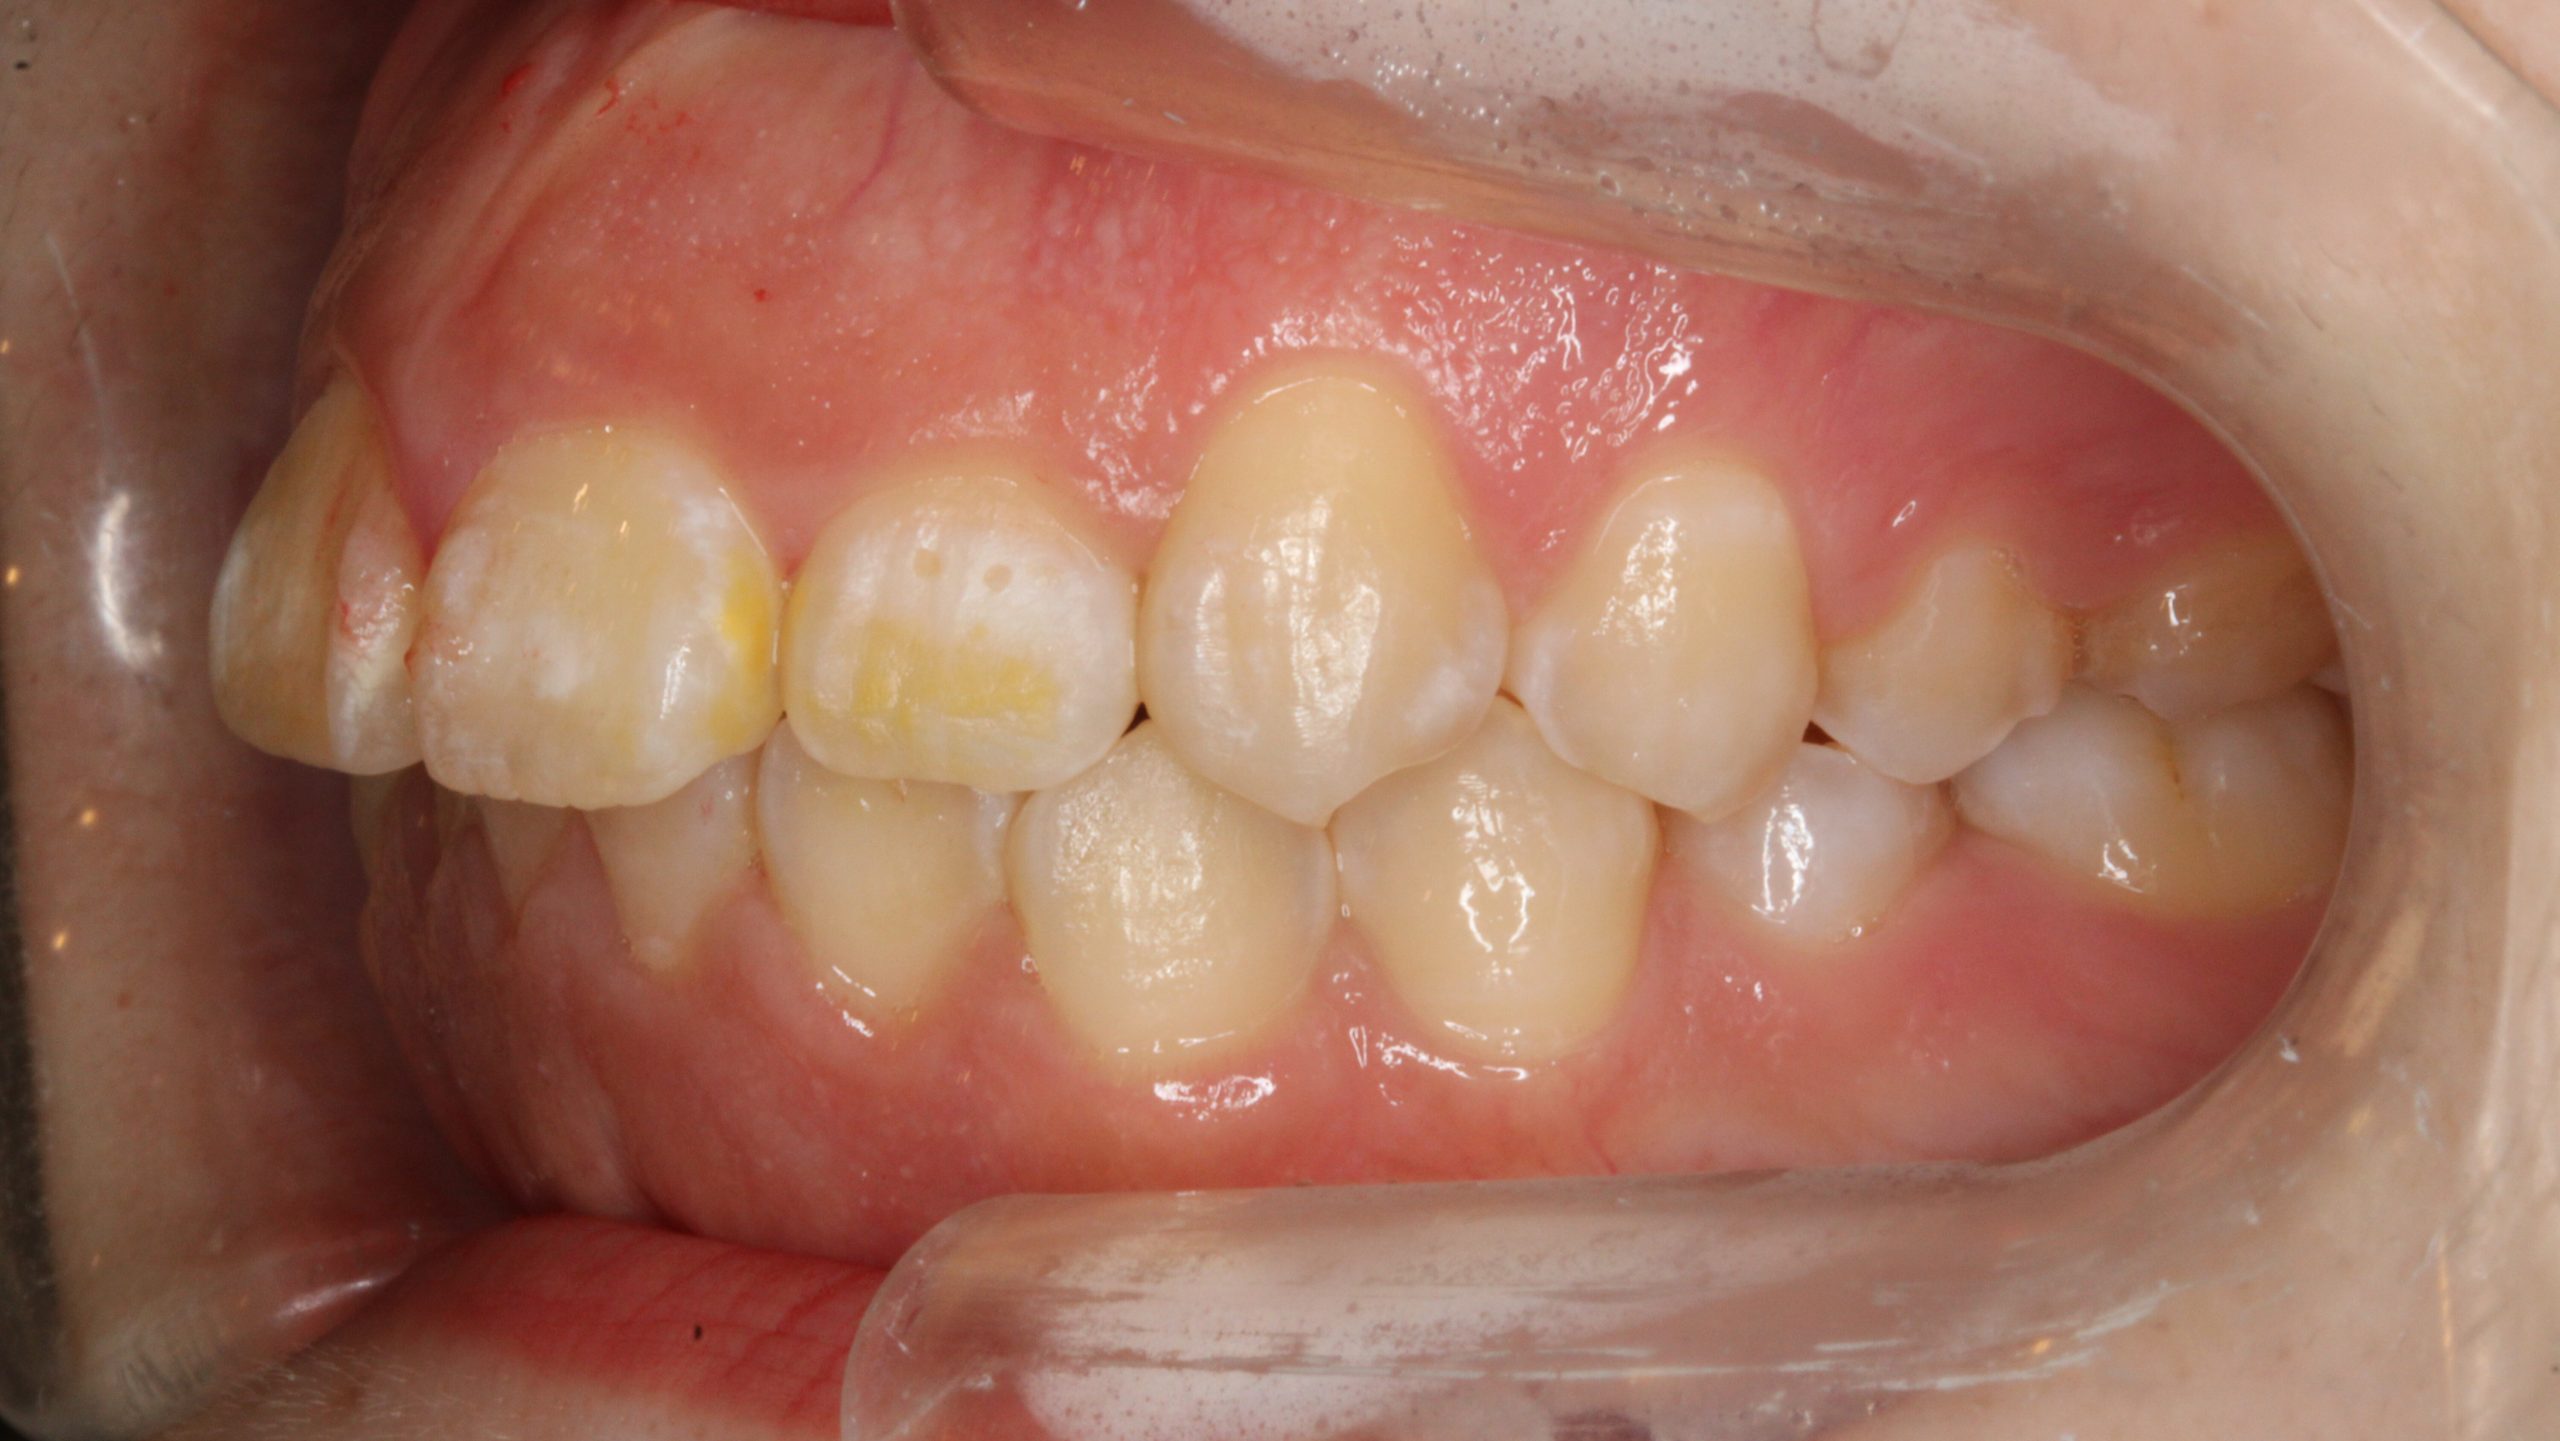

上の歯が出ている、嚙み合わせが悪い(治療期間:2年4か月/通院32回)

Before